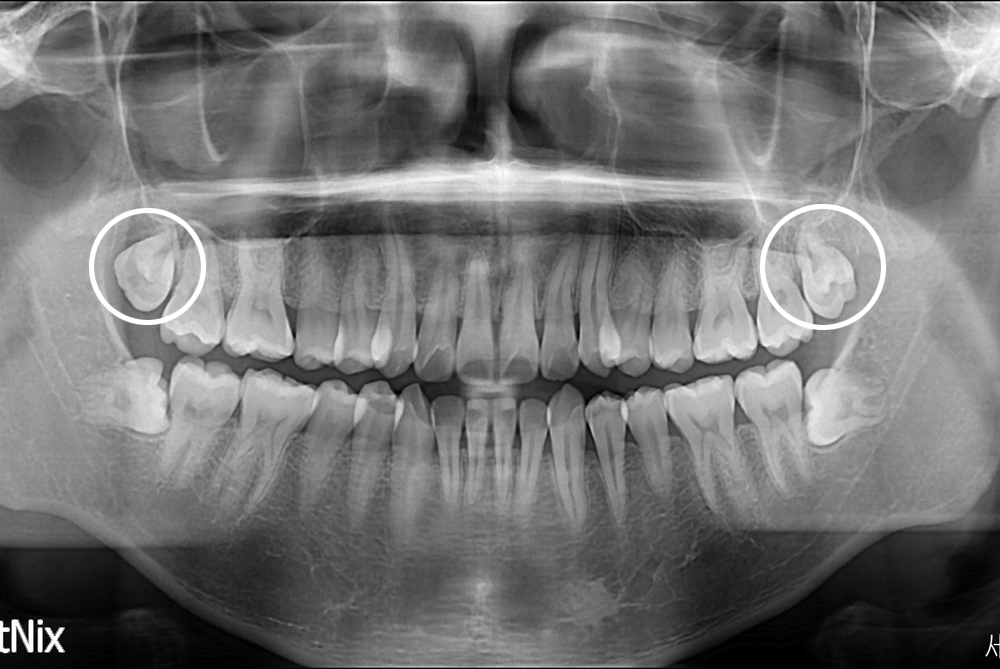

[사랑니] 난발치 사랑니 발치

치료전 : 2017-10-13